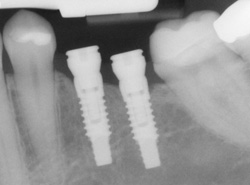

Implants

implantsIf you have missing teeth, it is crucial to replace them. Without all your teeth, chewing and eating can destabilize your bite and cause you discomfort. When teeth are missing, your mouth can shift and even cause your face to look older. Implants are a great way to replace your missing teeth, and if properly maintained, can last a lifetime!

An implant is a new tooth made of metal and porcelain that looks just like your natural tooth. It’s composed of two main parts: One part is the titanium implant body that takes the place of the missing root, and the second part is the tooth-colored crown that is cemented on top of the implant. With periodontal treatment, you can smile confidently knowing no one will ever suspect you have a replacement tooth.

implants processIn addition to tooth replacement, implants may be used to anchor dentures, especially lower dentures that tend to shift when you talk or chew. For patients with removable partial dentures, implants can replace missing teeth so you have a more natural-looking smile.